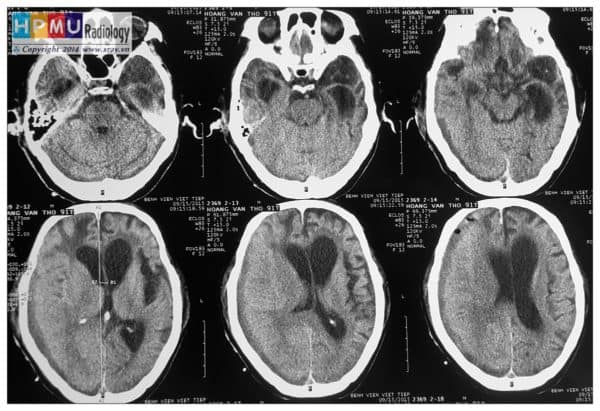

Chấn thương sọ não

» Thông tin: Nam giới – 91 tuổi.

» Lâm sàng: Chấn thương sọ não ngày thứ 7.